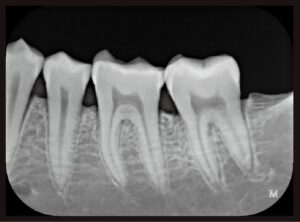

【デンタル画像(例)】

細部まで“拡大して確認”できます。